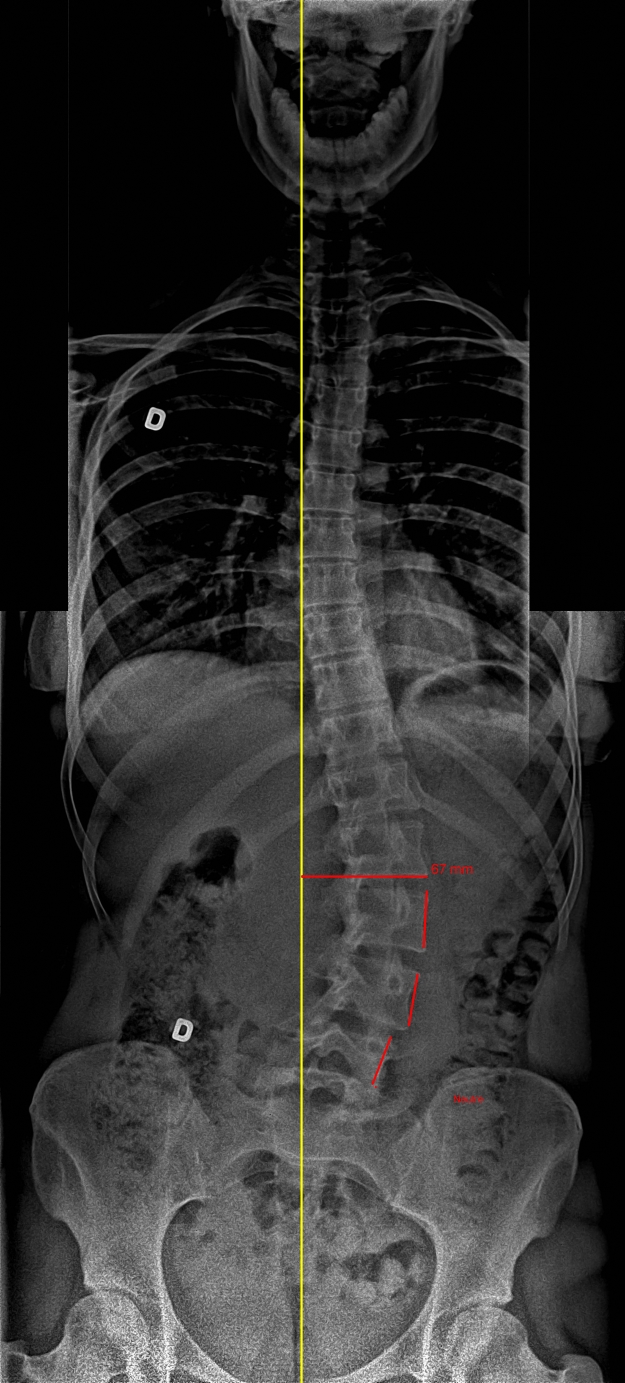

Decreasing the lever-arm effect (red line) by using the SpineCor® brace can help alleviate pressure on spinal joints and prevent further weakening of the spinal structure, which can lead to compression of the vital organs. |

In this case, the influence of gravity on the scoliosis has led to lateral listhesis. The second X-ray shows that the SpineCor® brace has decreased the lever-arm effect (see illustration above), thereby slowing the degenerative process.